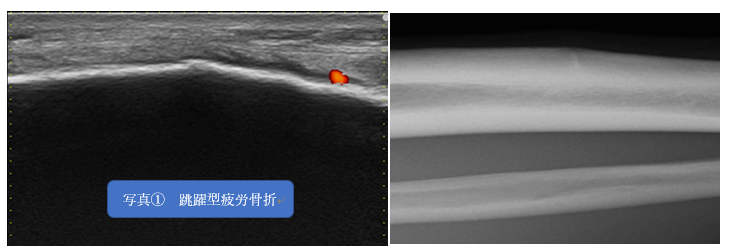

三段跳びが専門で脛骨の前が痛む、となれば怪しいのは跳躍型疲労骨折。

超音波エコーで強圧痛部位をみますと、やはり脛骨の骨皮質に不整像(連続性が途切れる部分)が認められました(写真①)。

これは跳躍型疲労骨折と判断し、すぐに医科で対診していただきました。

跳躍型疲労骨折は、疾走型と違い難治性です。

またやっかいなのは、圧痛は強いものの運動時痛がそれほど強くない場合もあり、歩行痛もすぐに軽快してしまうこともあります。

そうなると患者さんは、運動に復帰したがります。

必ずドクターの診察を受けるように指導し、ドクターの判断で運動復帰してもらうことが必要です。安易に判断すると、ある日ある時突然に完全骨折してしまうことがありますので要注意です。